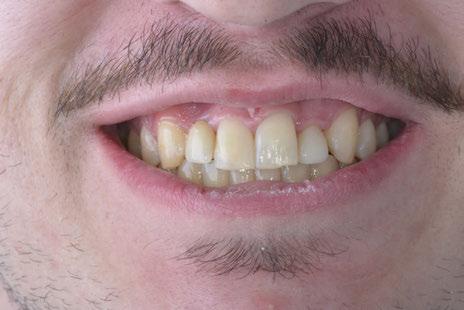

Protocolo Di2gitalArch® 2.0: Carga inmediata en el día en maxilar superior atrófico. Con Ziacom Galaxy, por el Dr. Luis Cuadrado Canals.